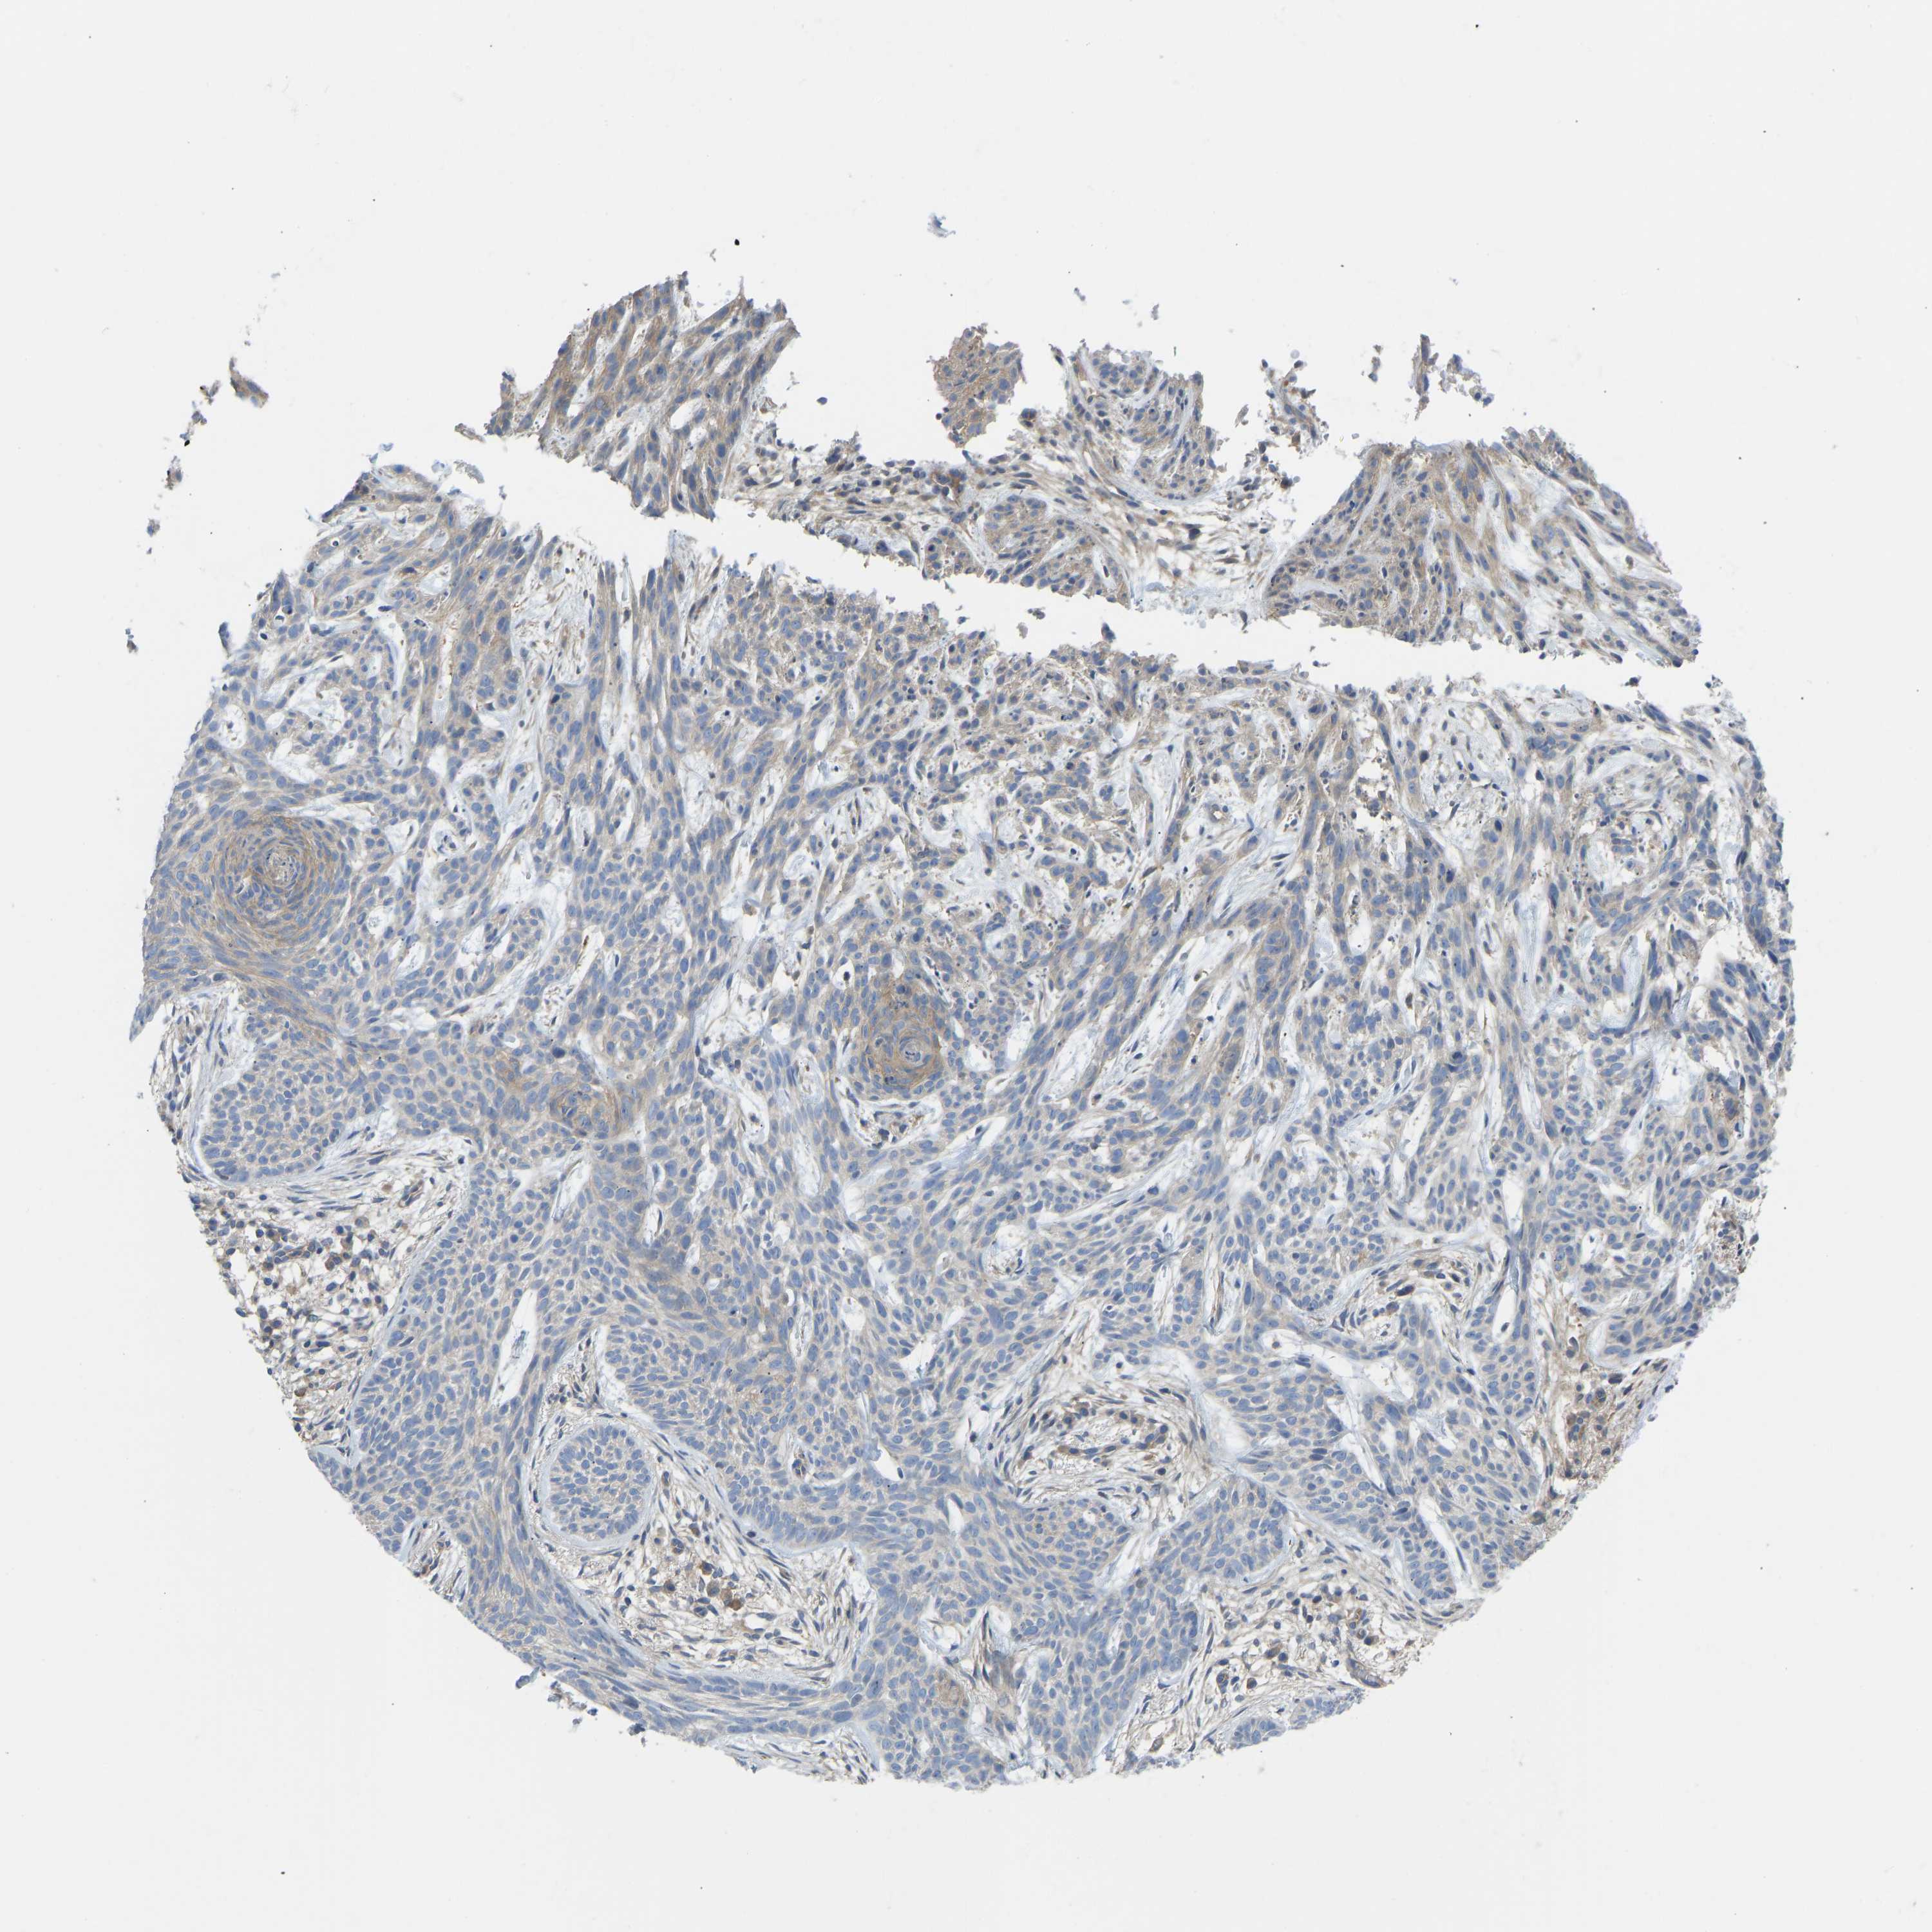

SKIN CANCER - Protein expressioni

A mouse-over function shows sample information and annotation data. Click on an image to view it in a full screen mode. Samples can be filtered based on level of antibody staining by selecting one or several of the following categories: high, medium, low and not detected. The assay and annotation is described here.

Each image is clickable and will lead to virtual microscopy that enables deeper exploration of all samples and also displays staining intensity scores, fraction scores and subcellular localization as well as patient and tissue information for each sample.

Antibody HPA012778

Basal cell carcinoma